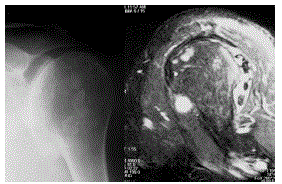

A presença de fragmentos osteocondrais (corpos livres) de base sinovial com baixo sinal na ponderação em T2, como representado na figura disponibilizada, refere-se a um diagnóstico.

Baseado na imagem disponibilizada, qual o seu diagnóstico?